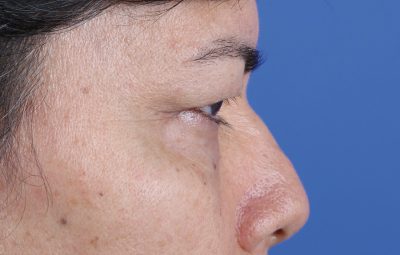

Es una ayuda diagnóstica complementaria que se utiliza para capturar imágenes de cualquier parte del cuerpo, aplicando técnicas que permitan obtener fotografías proporcionales, detalladas y nítidas; empleadas para medir, trazar, predeterminar y planear un proceso quirúrgico.

Es utilizada para crear imágenes del cuerpo humano, o partes de él, con propósitos clínicos que buscan revelar, diagnosticar y planear un tratamiento médico.